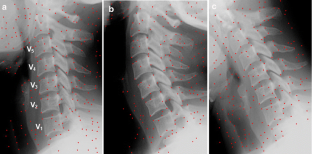

This study was conducted to evaluate a new method used to calculate vertebra orientation in medical x-ray images. The goal of this work is to develop an x-ray image segmentation approach used to identify the location and the orientation of the cervical vertebrae in medical images. We propose a method for localization of vertebrae by extracting the anterior—left—faces of vertebra contours. This approach is based on automatic corner points of interest detection. For this task, we use the Harris corner detector. The final goal is to determine vertebral motion induced by their movement between two or several positions. The proposed system proceeds in several phases as follows: (a) image acquisition, (b) corner detection, (c) extracting of the corners belonging to vertebra left sides, (d) global estimation of the spine curvature, and (e) anterior face vertebra detection.

Fig 2